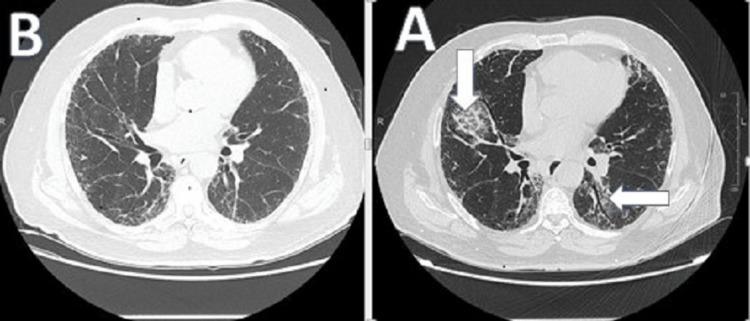

Metformin, a mainstay treatment for type two diabetes mellitus has several side effects, ranging from mild to life-threatening ones. One report has found the combination of metformin/glibenclamide a culprit for interstitial lung disease. Other studies have shown that metformin has a protective effect on the lungs. We report a rare case of a 64-year-old male who presented with progressive dyspnea while he was on metformin alone. He was diagnosed with eosinophilic interstitial lung disease (ILD). This was confirmed by a pulmonary function test (PFT), high-resolution chest computed tomography scan (HRCT), and bronchoscopy with bronchoalveolar lavage (BAL). Known causes for eosinophilic pneumonia were excluded, and the patient's condition improved significantly after withdrawing metformin. We report this case due to the rarity of the condition. In fact, this is the only case in the literature, of metformin as the sole agent causing eosinophilic pneumonitis.